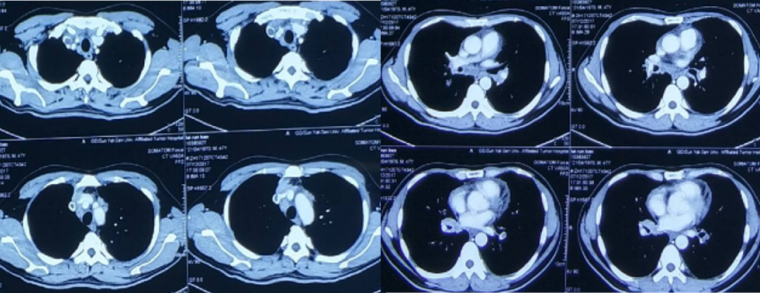

患者,男,47岁,因“咳嗽1月余,气促20余天,加重伴发热5天”,于2017年12月11日入我院。入院1月余前无明显诱因开始出现咳嗽、咳痰,为白色泡沫痰,无气促、咯血、呼吸困难,至当地医院经抗感染治疗后(具体不详)无好转,症状进行性加重。入院前20天出现活动后气促、呼吸困难,于2017年12月3日至广东某医院,查颈部+胸部+颅脑CT提示:左右肺纹理增多、增粗,见点索状、小片状、结节状增密阴影,边界模糊,考虑肺泡癌?转移瘤?炎症?纵隔多发肿大淋巴结,考虑转移瘤;心包积液;双侧胸腔积液;肝内多发病灶,考虑转移瘤(图1)。

2017年12月6日就诊于中山大学肿瘤防治中心,查WBC14.73×109/L,D-二聚体37.17 μg/ml。胸部CT提示:右下肺门区软组织影并右下肺阻塞性肺炎、肺不张,右下肺前外基底段胸膜下结节,考虑原发肺癌与转移瘤相鉴别;双肺叶弥漫粟粒、类结节,考虑转移瘤;双肺多发斑片影,部分呈磨玻璃密度,考虑炎症;双侧锁骨上窝、纵隔、双肺门多发淋巴结,考虑转移瘤;右侧颈静脉-右侧锁骨下静脉-右无名动脉内充盈缺损,考虑血栓可能性大,左肺动脉可见栓塞(血栓或癌栓)(图2)。